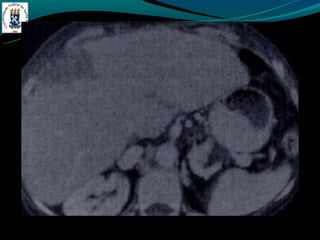

-TC: fígado com densidade > 70 HU – sobrecarga de ferro

-RM: Redução da intensidade do sinal em T1 e T2. hiperintenso

no baço.

HEMOCROMATOSE -Primária(hereditária) - Aumento da reabsorção gastrointestinal - 4ª e 5ª década de vida - DM, IC, artralgia… -Secundária(aumento do aporte) - Anemia crônica com múltiplas transfusões - Ingestão excessiva, porfiria, -TC: fígado com densidade > 70 HU – sobrecarga de ferro -Ouro coloidal, doença de Wilson, d. armaz. de glicogênio -RM: Redução da intensidade do sinal em T1 e T2. hiperintenso no baço. -Hemossiderose, d. de Wilson…